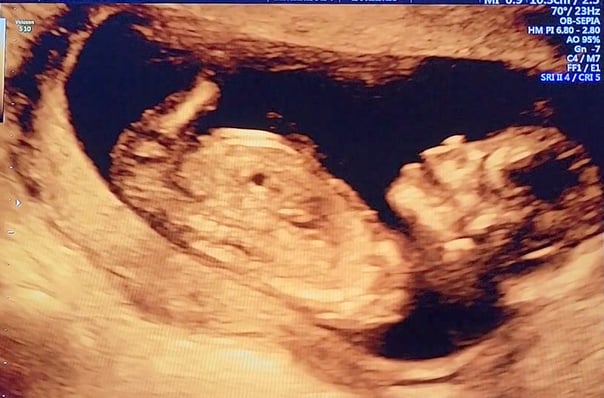

Essa fotinho é do meu primeiro ultrassom! Eu não tinha nem o tamanho de uma azeitona, e já me mexia todo, abria a boca e meu coração já batia bem forte!